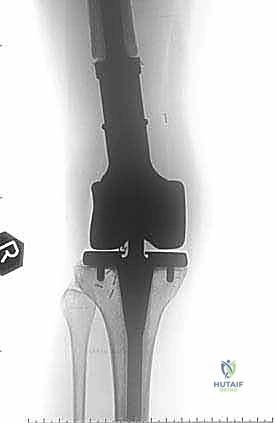

نقائل العظم الفخذي هي أورام ثانوية تنتشر إلى عظم الفخذ، مسببة الألم والكسور. يشمل علاجها الجراحي استعادة الوظيفة وتخفيف الألم من خلال التجريف والتثبيت بمسامير نخاعية أو الاستئصال وإعادة البناء بأطراف صناعية، ويتم ذلك على يد خبراء مثل الأستاذ الدكتور محمد هطيف في صنعاء.

الخلاصة الطبية السريعة: نقائل العظم الفخذي هي أورام ثانوية تنتشر إلى عظم الفخذ قادمة من أورام أولية (مثل الثدي، البروستاتا، الرئة، الكلى، أو الغدة الدرقية)، مسببة الألم المبرح والكسور المرضية التي تقعد المريض عن الحركة. يشمل العلاج الجراحي المتقدم استعادة الوظيفة، الحفاظ على استقلالية المريض، وتخفيف الألم بشكل جذري من خلال تقنيات مثل التجريف والتثبيت بمسامير نخاعية مع الأسمنت العظمي، أو الاستئصال الواسع للورم وإعادة البناء بأطراف صناعية كبرى (Megaprosthesis). يتم إجراء هذه الجراحات المعقدة بأعلى نسب النجاح على يد خبراء جراحة العظام والأورام، وعلى رأسهم الأستاذ الدكتور محمد هطيف في العاصمة اليمنية صنعاء، والذي يجمع بين الخبرة الأكاديمية والمهارة الجراحية الدقيقة.

هذا الجزء يتسع ليشكل اللقمتين الفخذيتين (Condyles) اللتين تتمفصلان مع عظم الظنبوب (القصبة) لتكوين مفصل الركبة. النقائل في هذه المنطقة تؤثر بشكل مباشر على ميكانيكا الركبة وتسبب آلاماً شديدة عند ثني أو فرد الساق. الجراحة هنا تتطلب دقة متناهية للحفاظ على أربطة الركبة (الصليبية والجانبية) أو استبدال المفصل بالكامل بمفصل صناعي للأورام إذا كان التدمير العظمي واسعاً.